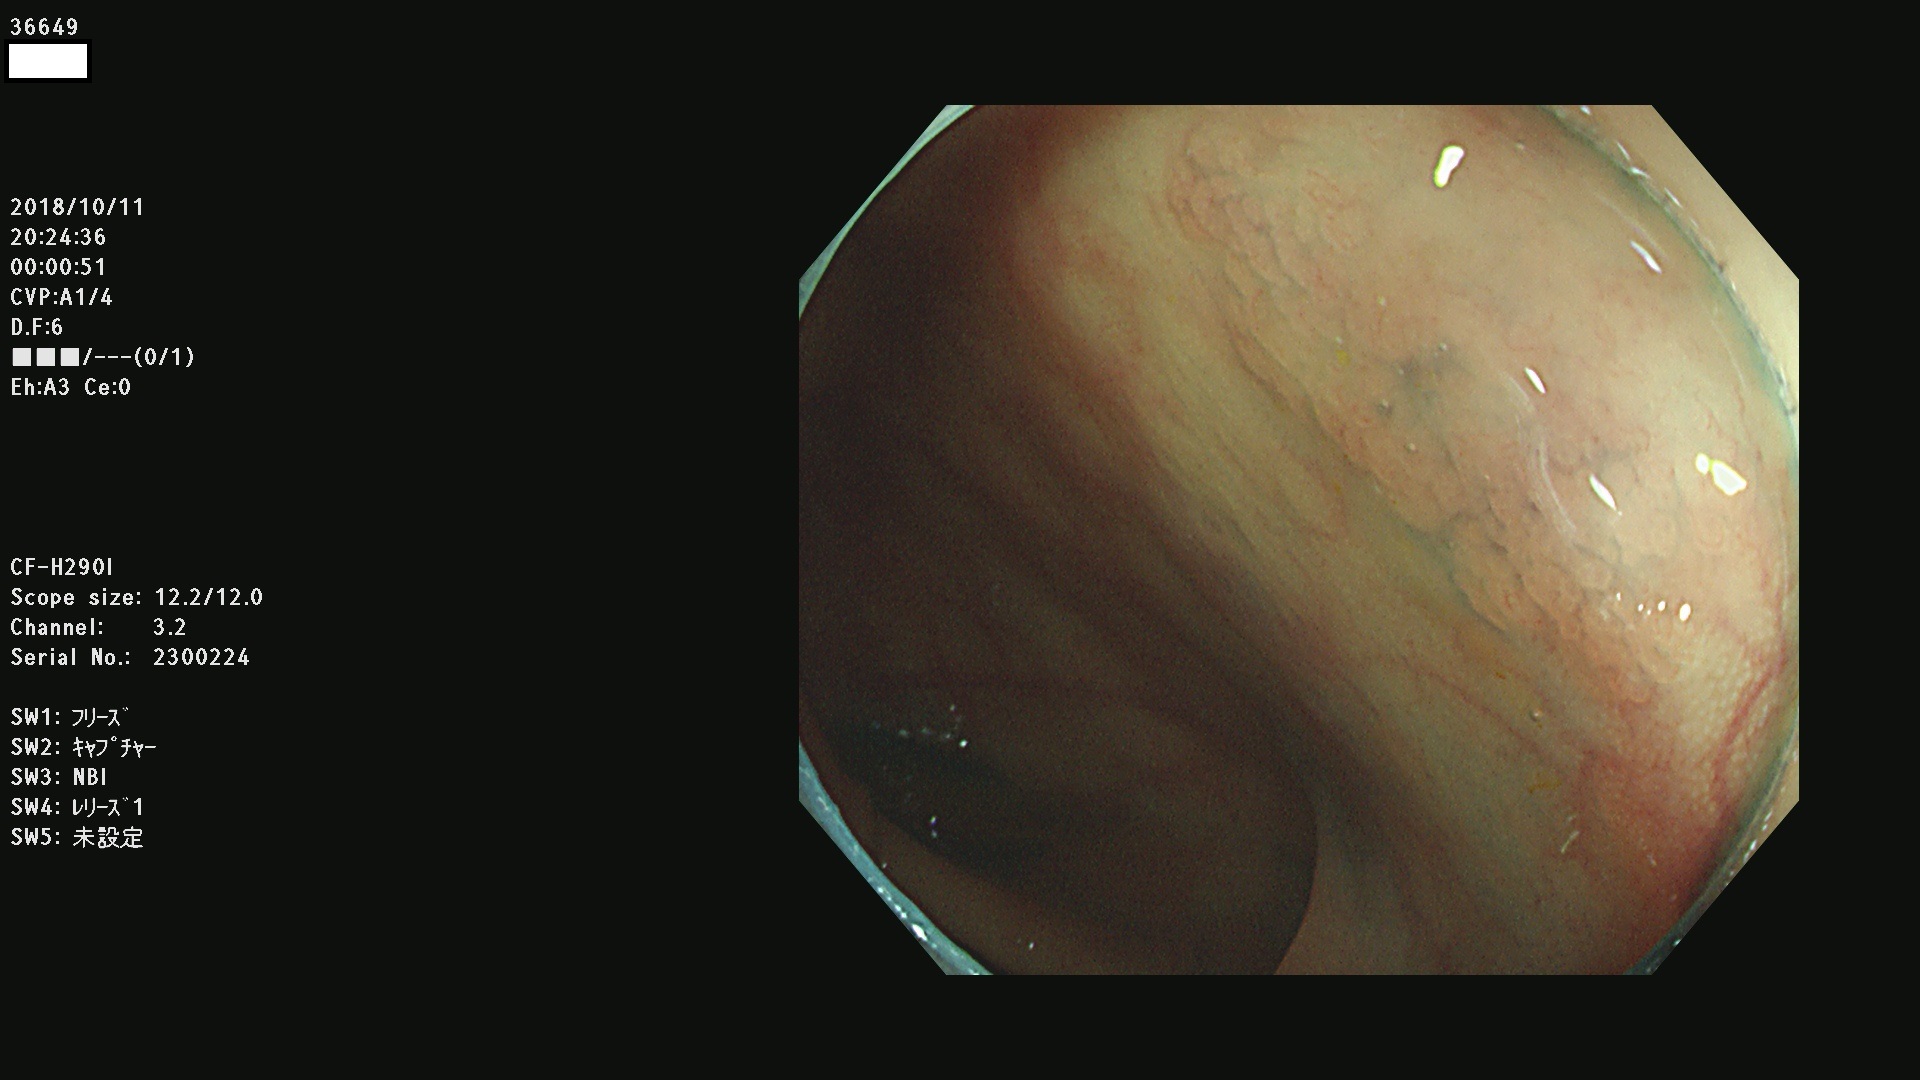

36600 36601 36603 36605 36606 36608 36609 36610 36611 36612 36613 36615 36617 36620 36621 36624 36625 36626 36627 36628 36629 36631(SSAPのみ) 36632 36633 36634 36636(SSAPのみ) 36637(SSAPのみ) 36639 36640 36642 36643 36644 36646 36647 36648 36649(SSAPのみ) 36650(SSAPのみ) 36652 36653 36654 36655(SSAPのみ) 36656 36657 36658 36659 36660 36661(SSAPのみ) 36665 36668 36669 36672 36673 36676 36677 36678 36679 36681 36682 36683 36684 36685 36687(SSAPのみ) 36691 36692 36693 36694 36695 36696 36697 36699(SSAPのみ)